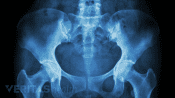

X-ray of the human pelvic bone.

Radiographic Tests for SI Joint Dysfunction